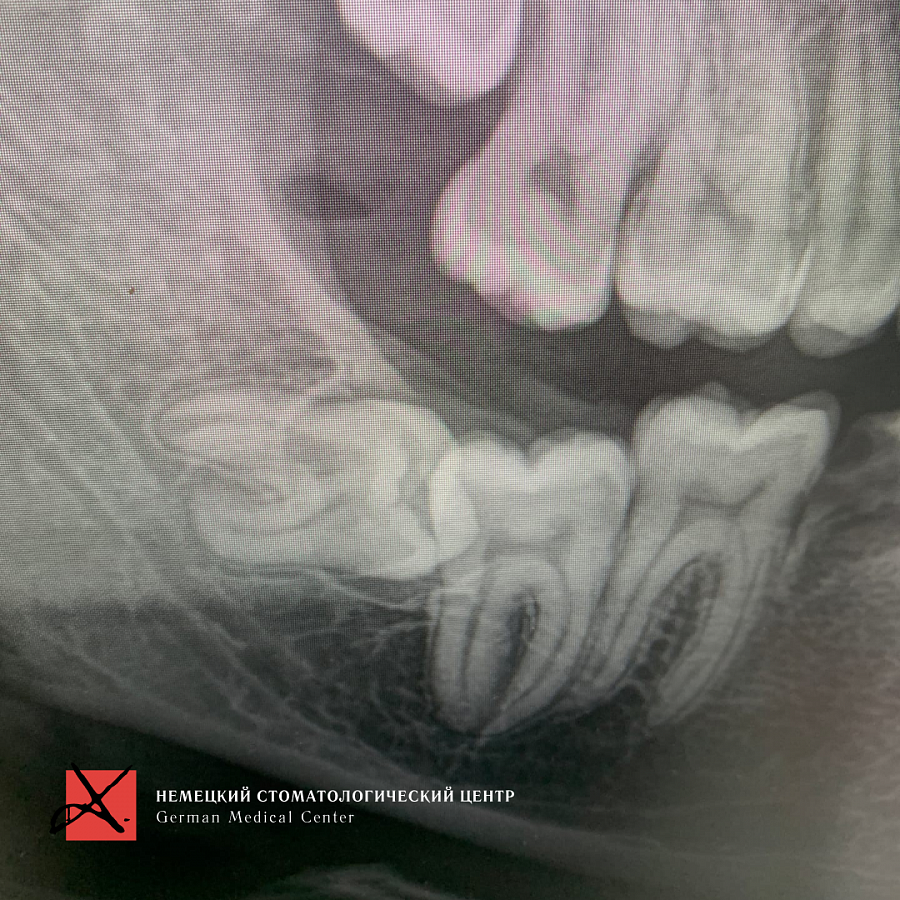

Пациент направлен врачом-ортодонтом для удаления зуба мудрости, который лежит горизонтально. Зуб мудрости мешал прорезаться седьмому зубу.

Доступ к восьмому зубу был сильно ограничен, что усложняло удаление. Но наш хирург успешно справился с задачей.